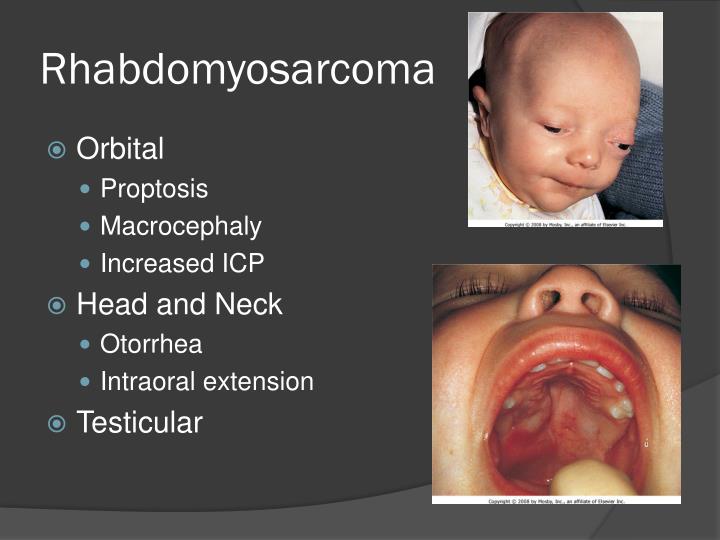

Rhabdomyosarcoma

Rhabdomyosarcoma

Rhabdomyosarcoma - 1.

rhabdomyosarcoma